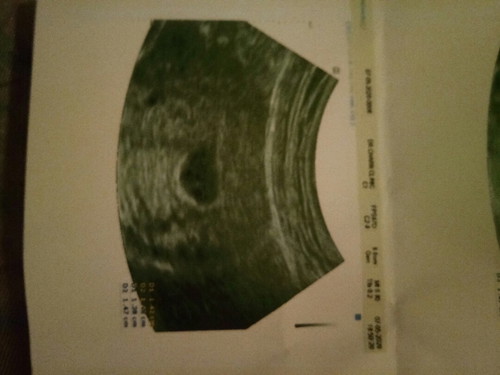

ยังไม่เจอตัวเด็กเลยคะ ไปครั้งแรกวันที่20เมษา คุณหมอบอกว่าท้องคะท้องได้4สัปดากว่าๆคะ แต่ยังเจอน้องเล็กๆยุคะ หมอนัดอีกทีวันที่4แต่เราไปวันที่7 หมอบอกว่ายังไม่เจอเด็กคะ แม่ๆบ้านไหนเจอแล้วคะ และได้กี่เซนคะ